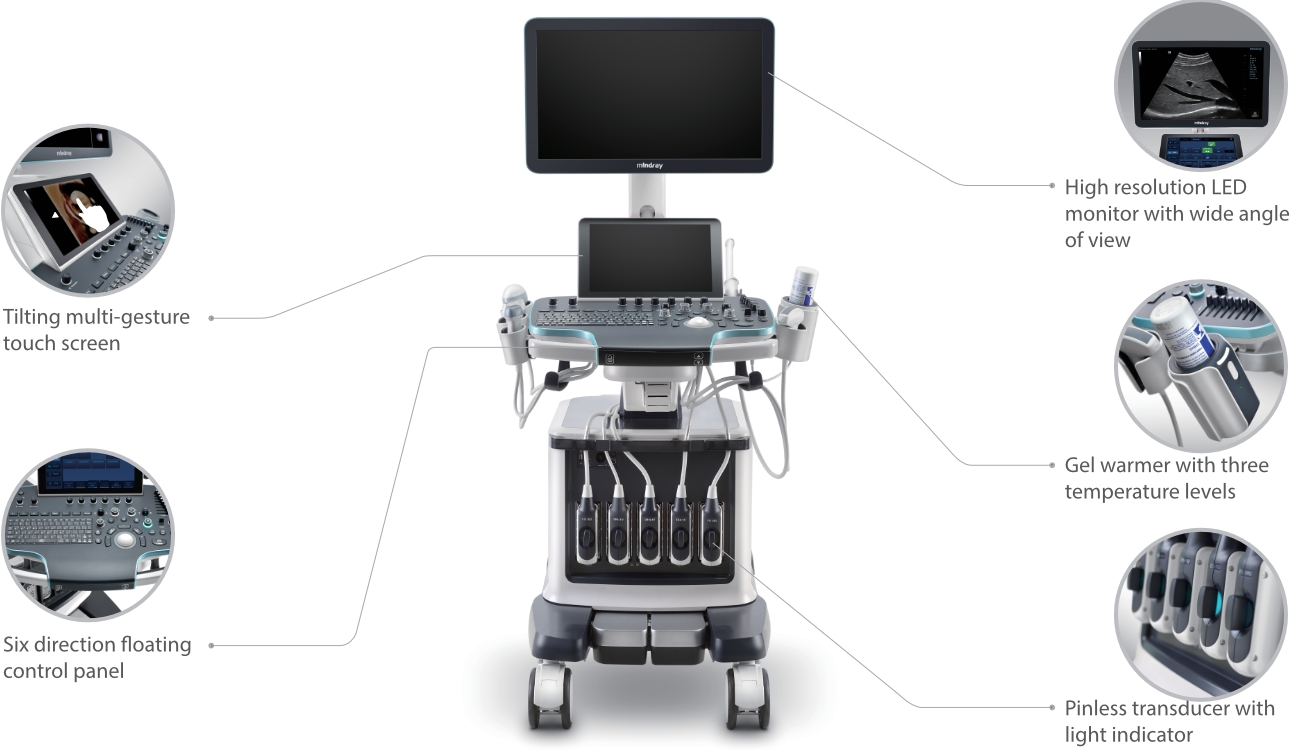

Обеспечивая качество изображения уровня премиум, Resona 7 также повышает клинические возможности исследования при помощи революционной системы V Flow, предназначенной для оценки гемодинамических показателей сосудов; обеспечивает интеллектуальное получение из 3D данных наиболее важных проекций для диагностики ЦНС плода. Сочетая в себе интуитивно понятное сенсорное управление с распознаванием жестов и все важные клинические характеристики, передовая система Resona 7 настоящая новая волна в сфере ультразвуковых инноваций.Благодаря перечисленным выше характеристикам, Resona 7 является доступным решением премиум-класса, которое удовлетворяет высоким требованиям клинической точности и эффективной диагностики в условиях современной перегруженной больничной среды.